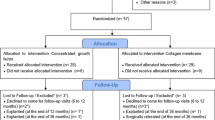

Patient recruitment took place between July 2020 and May 2022. As per the initial plan, forty patients were enrolled, all of whom received their final restorations. Six patients underwent simultaneous sinus grafting procedures. However, three patients did not complete the 12-month follow-up (2 in the control group, 1 in the test group). In the test group, one implant was lost six months after crown delivery, possibly due to overloading (any data from this patient were included). Additionally, one patient became unreachable, and another patient underwent the extraction of all teeth and implants for oncologic reasons alio loco. Figure 3 provides an overview of the enrollment and allocation process, while Table 1 describes the baseline assessments.

Primary clinical outcome - soft tissue height